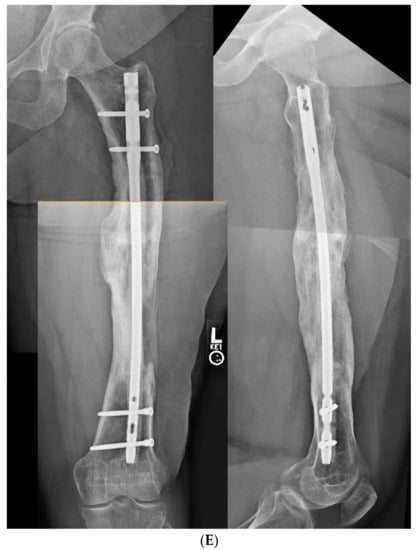

3.3. Case 3-Single-Plane Correction with Nail: Tibia

An adult male with no comorbidities presented with varus malunion following intramedullary tibial nailing, reporting symptomatic medial knee pain (Figure 8A). The CORA analysis revealed a varus deformity of 12 degrees. With a deformity in the coronal plane, surgical access was through an anterior approach using a focal dome osteotomy for correction. The anterior compartment was elevated, and a drill bit was placed in the CORA, with a parallel drill guide used to draw the arc with a second drill bit. The osteotomy was completed with an osteotome. The alignment was maintained during reaming using a temporary plate (Figure 8B). The patient underwent compression nailing using a magnetic motorized nail, allowing for subsequent compression as needed after discharge (Figure 8C). The patient felt pain-free at 12 weeks, yet was encouraged to return for regular follow-up examinations and X-rays until radiographic healing. Patient lost to follow-up after 6 months (Figure 8D).

Figure 8.

(A) Adult male with varus malunion deformity after a prior tibia fracture and nailing. (B,C) Patient underwent focal dome osteotomy with compression nailing using a magnetic motorized nail for early and subsequent nail compression. (D) Patient declined to follow-up after 12 weeks, citing absence of pain. Patient returned at 6 months at request of surgeon, still without pain. Magnetic nail recompressed. Patient lost to follow-up after 6 months.